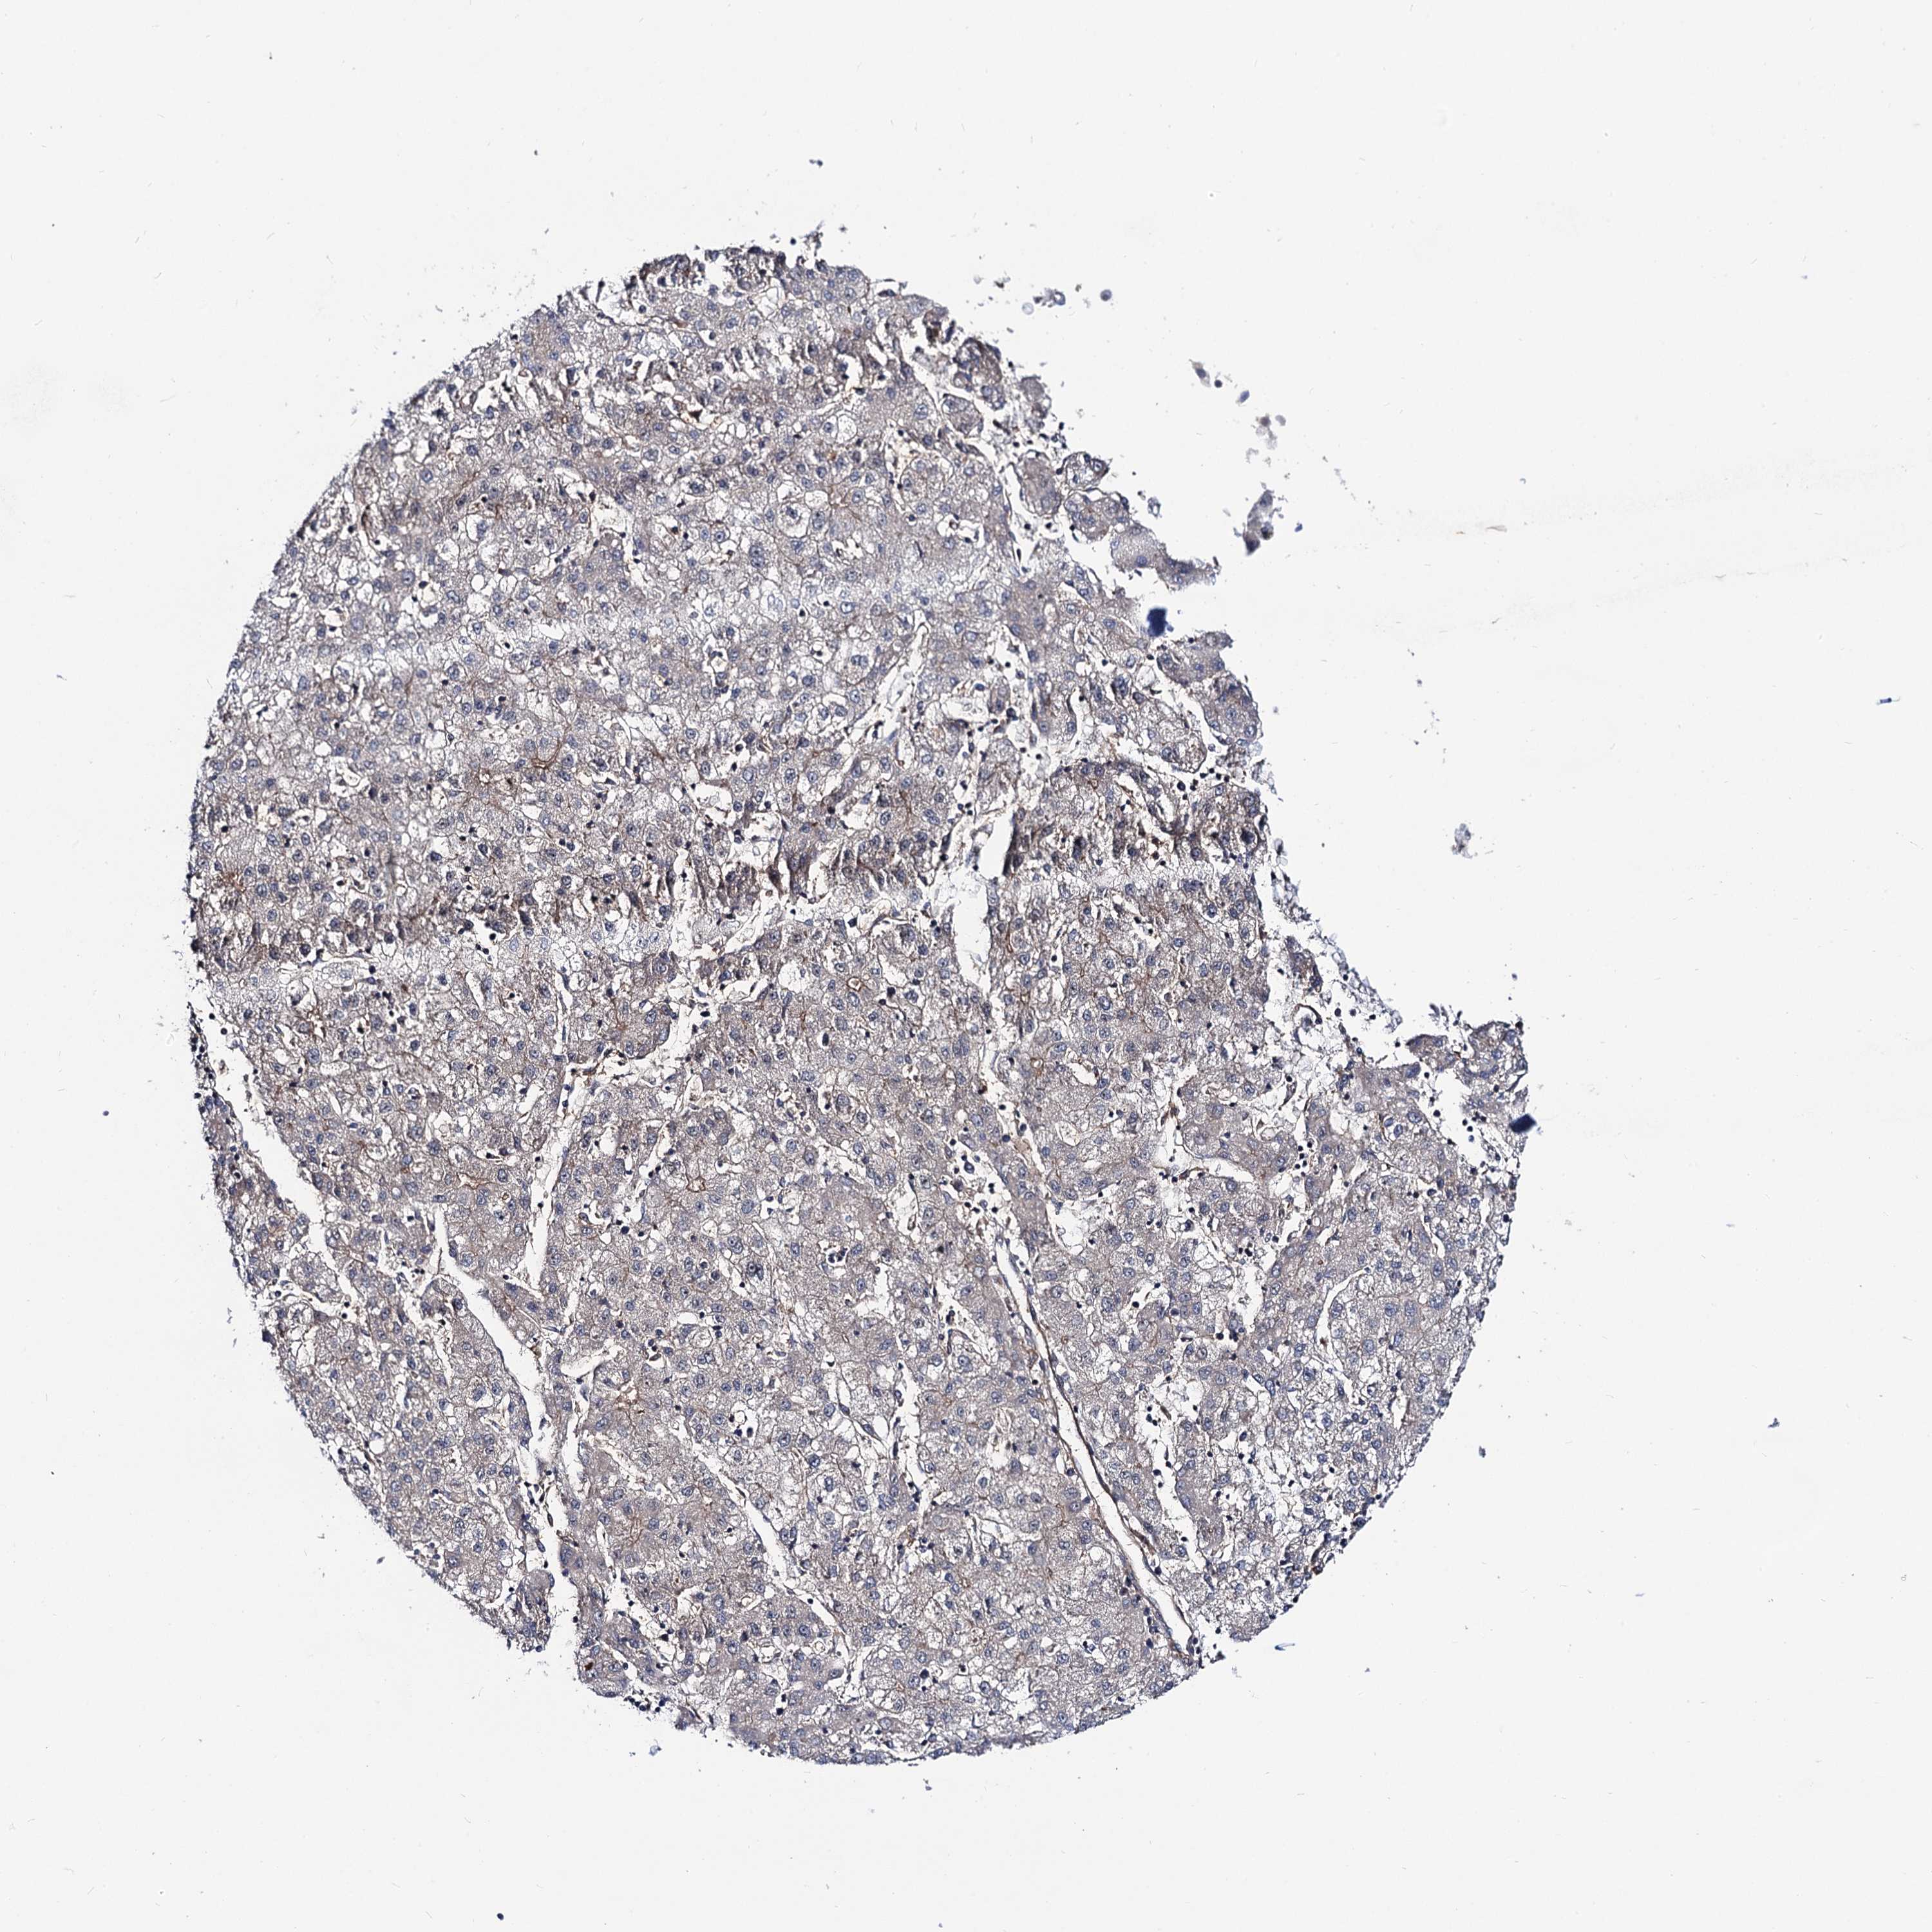

LIVER CANCER - Protein expressioni

A mouse-over function shows sample information and annotation data. Click on an image to view it in a full screen mode. Samples can be filtered based on level of antibody staining by selecting one or several of the following categories: high, medium, low and not detected. The assay and annotation is described here.

Note that samples used for immunohistochemistry by the Human Protein Atlas do not correspond to samples in the TCGA dataset.

Antibody stainingi

Antibody staining in the annotated cell types in the current human tissue is reported as not detected, low, medium, or high, based on conventional immunohistochemistry profiling in selected tissues. This score is based on the combination of the staining intensity and fraction of stained cells.

Each image is clickable and will lead to virtual microscopy that enables deeper exploration of all samples and also displays staining intensity scores, fraction scores and subcellular localization as well as patient and tissue information for each sample.

Cholangiocarcinoma

Carcinoma, Hepatocellular, NOS